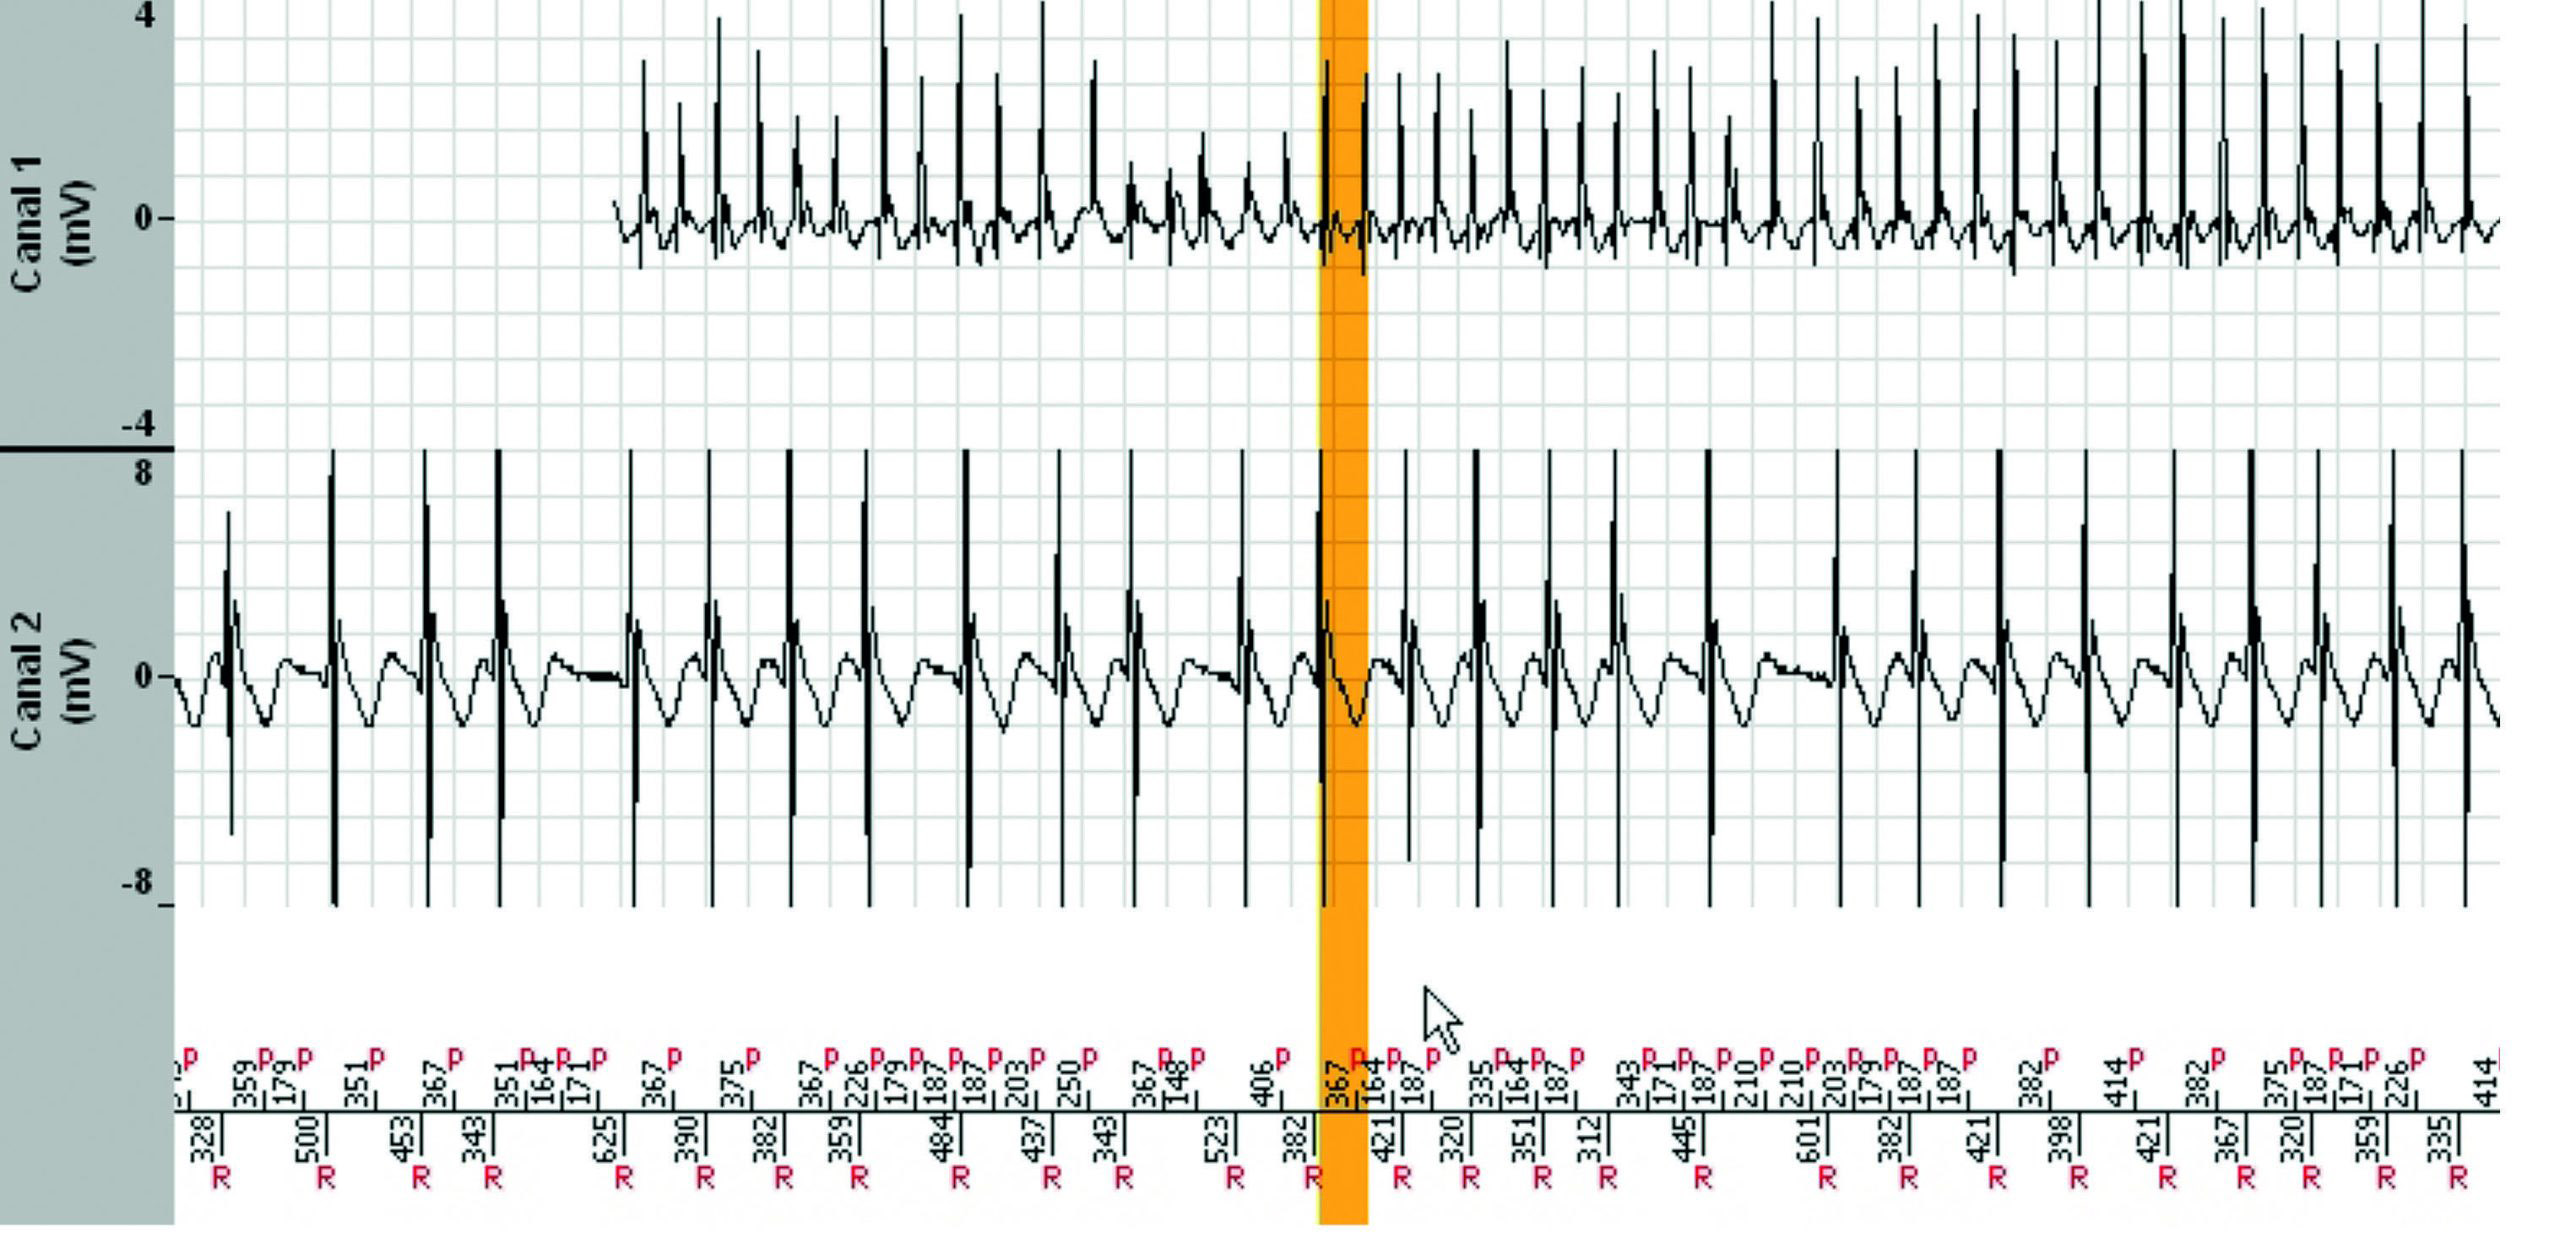

L'épisode a duré 7 minutes et 38 secondes et le tachogramme ci-dessous ne montre que les 3dernières minutes. Pendant les 4 minutes et 30 secondes précédentes, la fréquence ventriculaireest parfaitement stable dans la zone de TV lente.